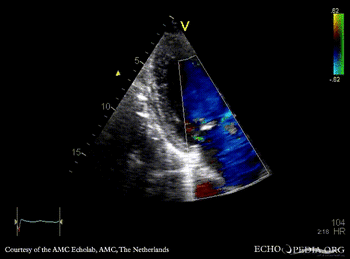

Endocarditis of mitral valve

A5CH A5CH: Color doppler, severe mitral regurgitation